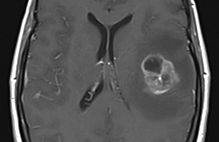

A 60-year-old woman had had a bilateral mastectomy two years ago, with no subsequent chemotherapy or radiation. She described her cPMP as “a barbed wire bra” on the front with several more painful spots, noted as the circle in Figure 1. Before treatment, her pain was 8-10/10, which decreased to 0-2/10 after five treatments, each lasting 45 minutes. She resumed painting and had a relatively more normal life, and was able to taper off and eventually stop her opioids. Her pain returned four months later and was successfully retreated (Figure 1). Her cancer subsequently metastasized to bones and became her dominant issue.